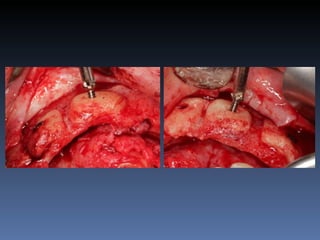

BOX 1

Diagnóstico: Desdentada total maxila

já reabilitada com “All-on-four” híbrido;

periimplantite dos implantes anteriores.

Plano de tratamento:         Remoção dos implantes

anteriores, instalação de dois implantes Zigomáticos

e dois implantes posteriores na tuberosidade.